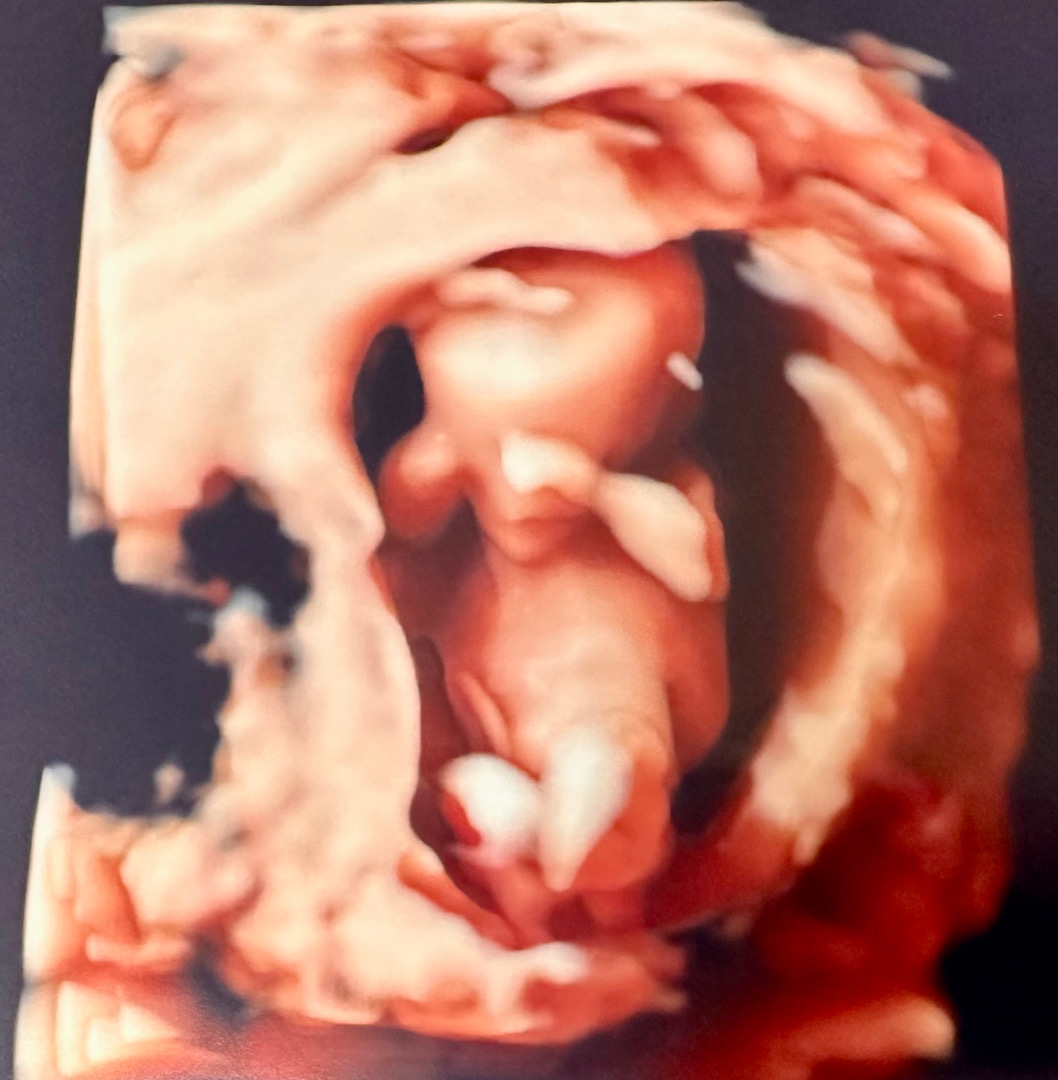

13주 2일, 1차 기형아 검사!

오늘 1차 기형아 검사를 하고 왔습니다! 정밀촘파실에는 배우자(보호자)가 동행할 수 없다고 해서 밖에서 대기하고 있었는데, 촘파실 쌤이 나중에 불러주셔서 와이프랑 같이 설명 듣고 나왔네요! 자세가 아쉽다고 하셨지만, 다른 이상은 없어 보인다고 하셨어요! 휴 ㅠ 1차 검사에서 가장 중요하게 생각했던 목투명대 두께도 1mm로 정상범위라고 하셨고, 코도 엄빠 닮아 오똑하지 않았..지만 보여서 다행(?)이었어요! ㅎㅎ 말발굽소리 같은 심장소리도 들었고, 머리뼈 대칭, 뇌 모양, 뇌심실, 경부길이, 태반형성, 탯줄 흐름성 등 다 정상이라고 해서 얼마나 다행이었던지.. ㅎㅎ 아가 크기는.. 잔뜩 웅크리고 있어서 주수보다 좀 작게 나왔네요 (6.11cm 12w6d) 목투명대 검사 촘파 사진을 못 받아서, 각도법으로 성별을 예측할 수 없게 되었고, 정밀촘파도 손으로 얼굴을 가리고, 양발로 아빠다리 하고 있어서 성별은.. 미궁 속으로..ㅎㅎ 저흰 니프티 검사를 신청해놔서, 체혈하고 귀가 했습니다! 결과는 약 2주 정도 뒤에 알 수 있다고 해서 담번 진료는 3주(?) 뒤로 예약이 잡혔어요 ㅋㅋ 3주 뒤 니프티 검사에서 이상이 없다면, 신경관결손검사를 마지막으로 안심할 수 있는 단계로 접어드는 것 같더라구요 벌써 1/3 왔는데, 2/3 금방 가겠죠? ㅎㅎ (긍정적인 마인드!!)